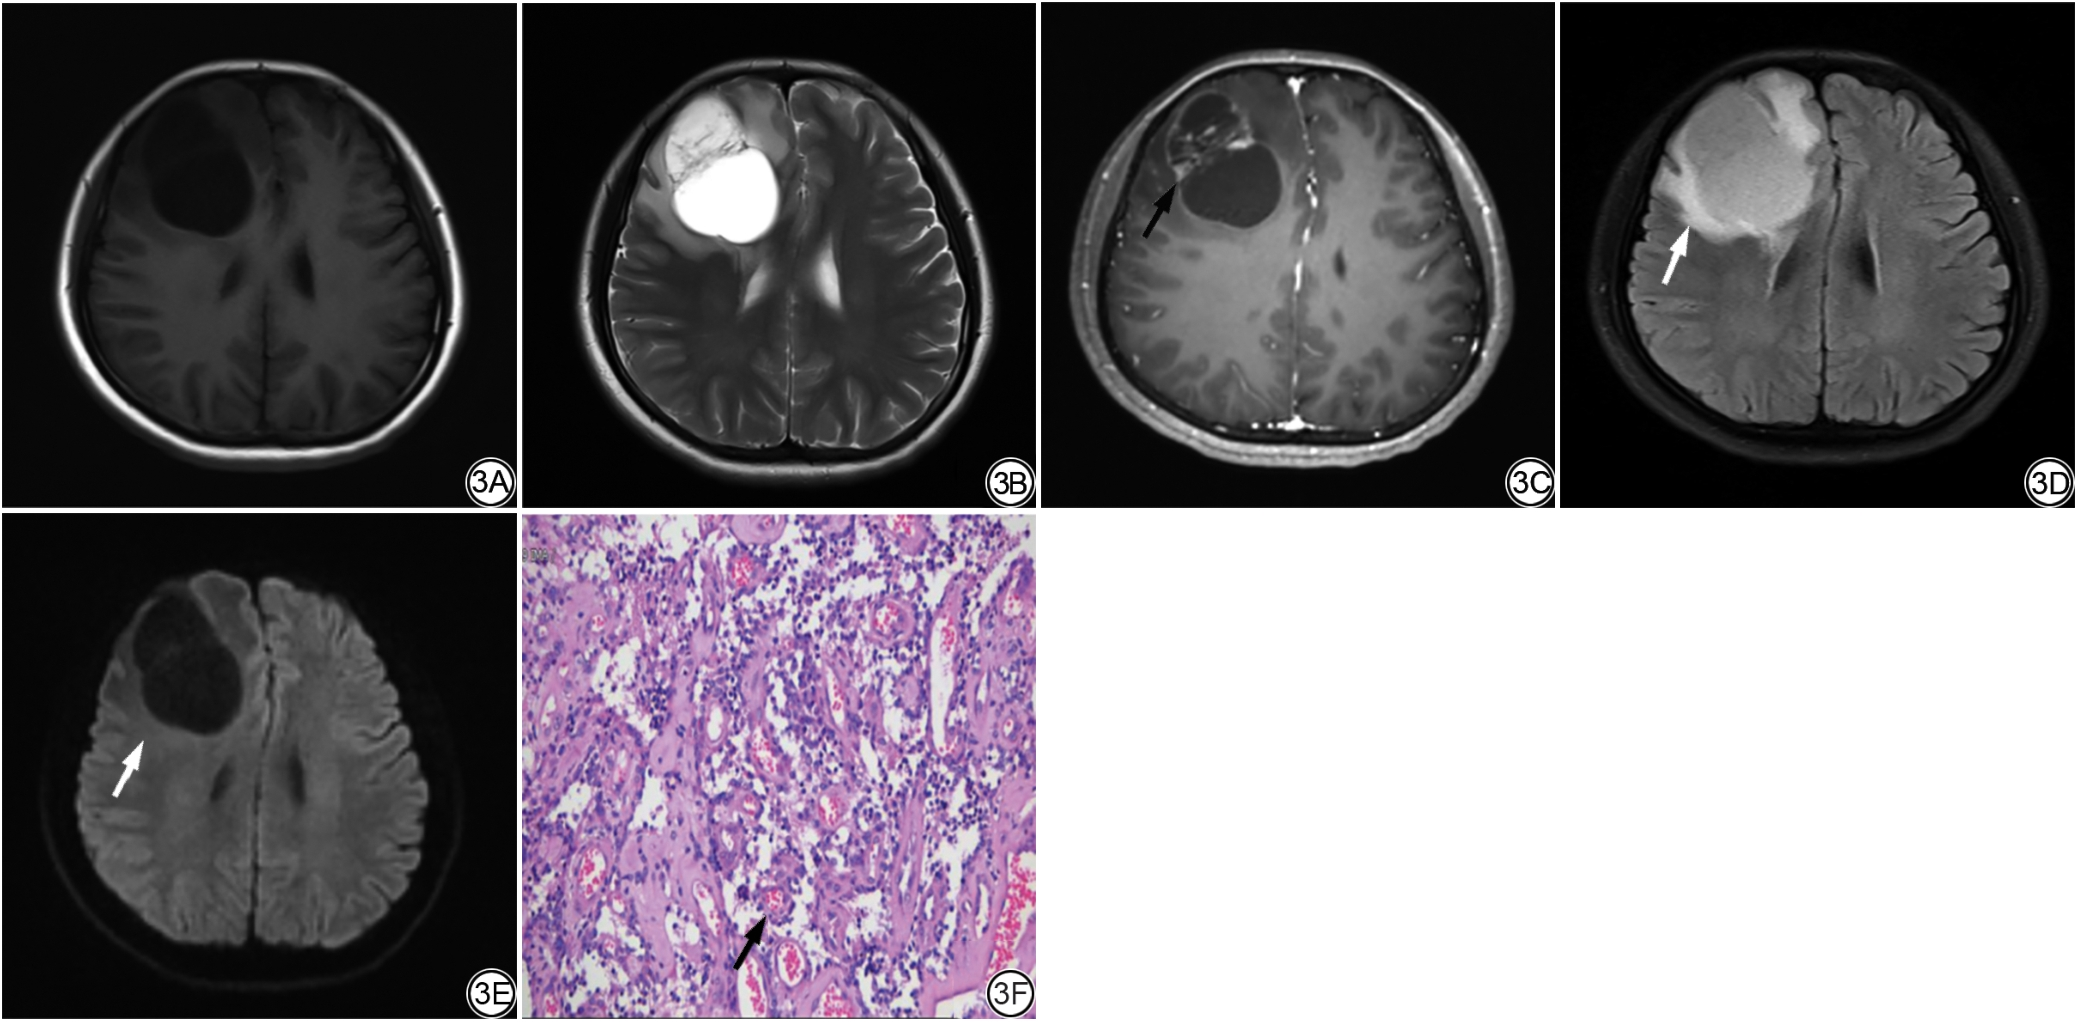

图4  女,20岁,左侧顶叶IEE,WHO分级3级,Ki-67增殖指数40%(高表达),VASARI总分为87。4A~4B分别为T1WI、T2WI图像,病灶呈多囊囊实性,T1WI呈等稍高信号影伴内部低信号区,T2WI示中央呈高信号、外周呈稍高信号;4C:CE-T1WI图像,病灶呈不均匀花环形强化,强化边缘(F11,箭)厚度为厚(4分);4D~4E分别为FLAIR、DWI图像,瘤周较大范围不规则水肿影,FLAIR呈高信号,DWI呈等信号,瘤周水肿(F14,白箭)百分比为68%~95%(6分);4F:病理图(HE ×200)可见肿瘤细胞呈放射状排列环绕血管生长,形成假菊形团结构(黑箭)及真菊形团结构(红箭),肿瘤细胞排列密集,胞核增大,异型性明显,中央可见大范围坏死区(均匀粉染区域)。IEE:颅内脑室外室管膜瘤;VASARI为伦勃朗视觉感受图像;CE-T1WI:增强T1加权成像;FLAIR:液体衰减反转恢复成像;DWI:弥散加权成像。

Fig. 4  Female, 20 years old, with left parietal lobe IEE, WHO grade 3, Ki-67 proliferation index 40% (high expression), and a VASARI total score of 87. 4A-4B: T1WI and T2WI images show a multicystic and solid lesion. On T1WI, the lesion presents with isointense and slightly high signal intensity accompanied by internal low signal areas. On T2WI, the central region shows high signal intensity, while the periphery exhibits slightly high signal intensity. 4C: CE-T1WI image demonstrates heterogeneous, ring-like enhancement of the lesion. The thickness of the enhancing margin (F11, arrow) is thick (4 points). 4D-4E: FLAIR and DWI images reveal an irregular, extensive area of peritumoral edema. The edema appears hyperintense on FLAIR and isointense on DWI. The percentage of peritumoral edema (F14, white arrow) is 68%-95% (6 points). 4F: Histopathological image (HE × 200) shows tumor cells arranged radially around blood vessels, forming pseudorosette structures (black arrow) and true rosette structures (red arrow). The tumor cells are densely packed with enlarged nuclei, marked atypia, and a large central area of necrosis (uniformly eosinophilic region). IEE: intracranial extraventricular ependymoma; VASARI: visually accessible Rembrandt images; CE-T1WI: contrast-enhanced T1-weighted imaging; FLAIR: fluid-attenuated inversion recovery; DWI: diffusion-weighted imaging.